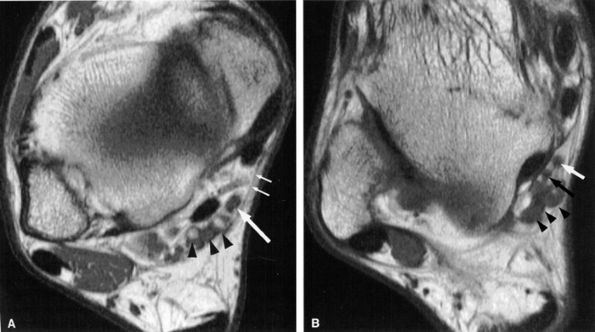

FIGURE 6.56 ● Neuropathy of the inferior calcaneal nerve (Baxter's neuropathy) in a 66-year-old patient with tarsal tunnel varicosities. Sagittal (A) and axial (B) T1-weighted images of the ankle demonstrate denervation atrophy of the abductor digiti quinti muscle (asterisk). (C and D). Normal abductor digiti quinti muscle (asterisk) in an asymptomatic patient for comparison.